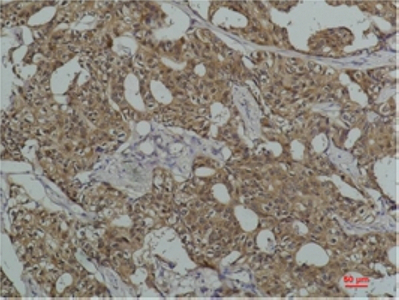

IHC 1/50-1/100 Human,Mouse,Rat